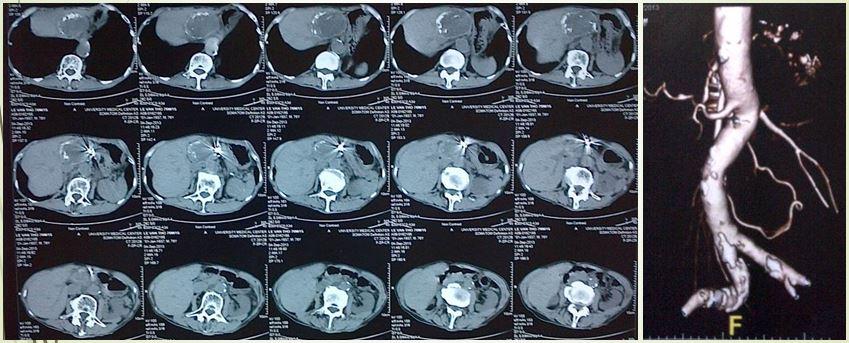

Ca lâm sàng đầu tiên BS Cường chia sẻ là một bệnh nhân nam 30 tuổi, nhập viện do bị đau đầu, tăng huyết áp. 2 tuần trước khi nhập viện anh đau khắp đầu mức độ trung bình, không nôn ói, không thay đổi tri giác, không yếu liệt, không tiểu máu, không đau bụng. Thế nhưng huyết áp lại ở mức cao 180mmHg. Hỏi kỹ bệnh sử thì anh có chấn thương bụng cách đó 8 năm do tai nạn giao thông: vỡ ruột, phẫu thuật nối ruột phải nằm viện 5 tháng.

Hình CT có gì đó bất thường ở thận phải, chưa biết có liên quan tới chấn thương cũ hay không vì bệnh nhân không ghi nhận tiểu máu. Đây là điều bất thường vì đa số các vấn đề: bướu máu trong thận, rò động tĩnh mạch thận sau mổ nội soi, ung thư trong thận thường gây chảy máu, và bệnh nhân sẽ thấy tiểu ra máu

Hình ảnh DSA cho thấy có một vị trí thông động tĩnh mạch, làm cho lưu lượng tưới máu đến nhu mô thận giảm đáng kể, từ đó có thể giải thích tại sao bệnh nhân tăng huyết áp dù tuổi còn trẻ Kết quả siêu âm bụng tổng quát không ghi nhận bất thường, siêu âm động mạch thận: Nghi ngờ rò động mạch thận. Xét nghiệm máu trong giới hạn bình thường. Bác sĩ chẩn đoán: tăng huyết áp người trẻ – rò động tĩnh mạch thận. Câu hỏi đặt ra cho các bác sĩ là phải làm gì? Nếu can thiệp không thành công thì phẫu thuật, nhưng năm 2006 phẫu thuật thận cũng rất khó khăn. Các bác sĩ quyết định cố gắng can thiệp nội mạch, dùng keo, dùng bóng, dùng tất cả phương tiện có trong tay lúc đó, cuối cùng đã bít được chỗ thông nối động mạch thận và tĩnh mạch chủ.

Sau can thiệp, huyết áp bệnh nhân trở về bình thường, hết sức vui vẻ vì không cần uống thuốc hạ huyết áp nữa, và chi phí phải thanh toán cho ca can thiệp cũng rất thấp.